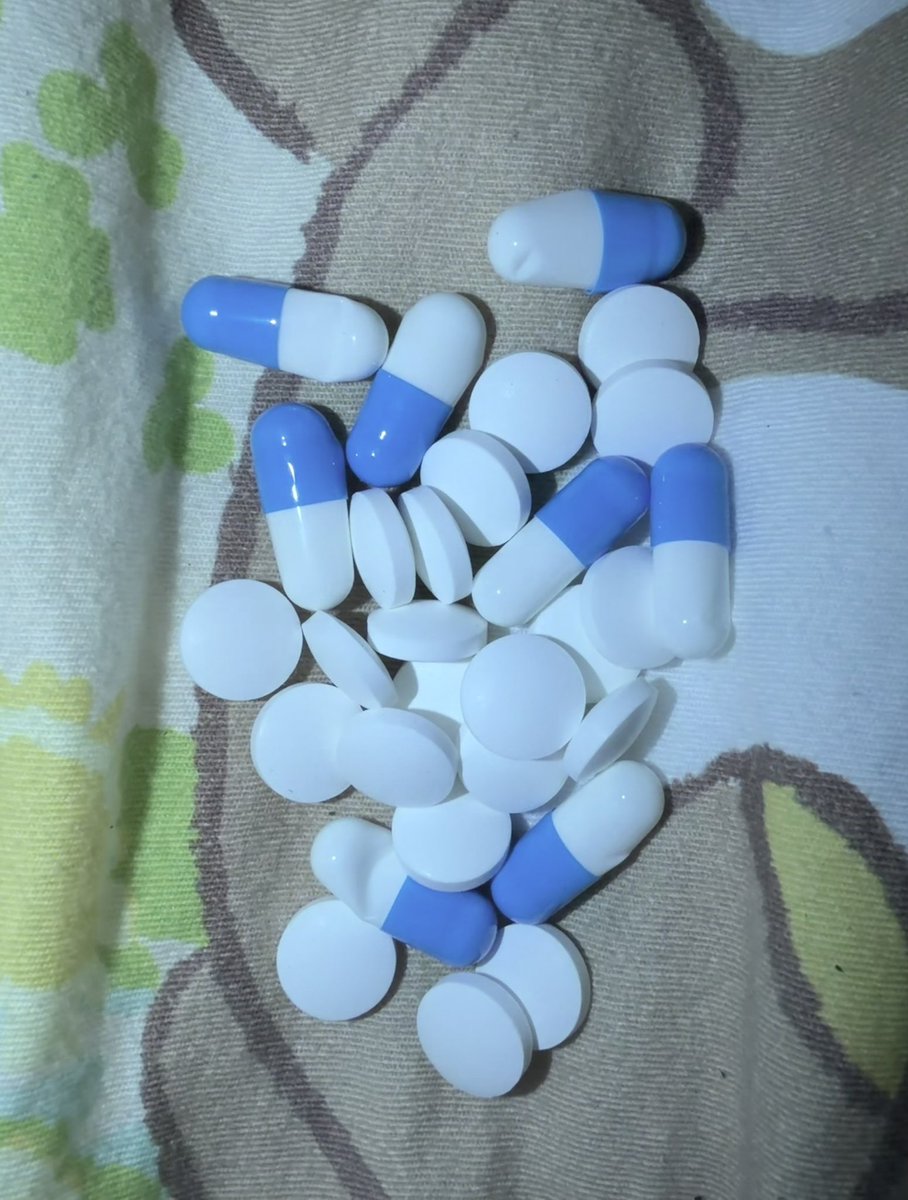

对于药物过量引起的中枢神经系统副作用,有一些不常见或常见的药物来控制症状。

评论区欢迎补充 https://t.co/7S4tGVDEM5